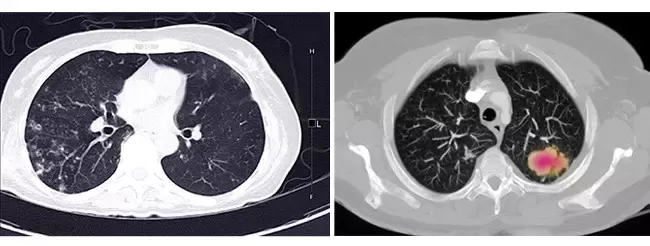

Các bệnh lý có thể hưởng lợi từ công nghệ xạ trị hiện đại trên hệ thống máy gia tốc Elekta Infinity

Xạ trị là phương pháp điều trị sử dụng các tia bức xạ năng lượng cao nhằm tiêu diệt tế bào ung thư. Theo số liệu của Cơ quan Năng lượng Nguyên tử Quốc tế ...